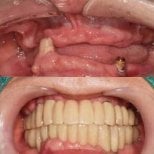

- Check reviews and patient photos. Look for real before-and-after cases and feedback from international patients.